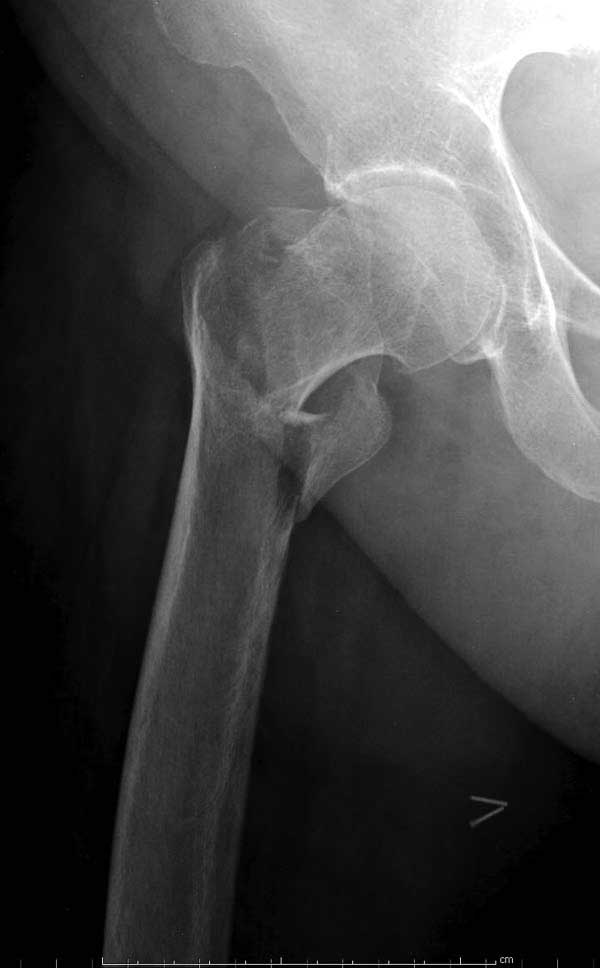

Банальный рутинный перелом чрезвертельной зоны лечимый DHS.

А по картинке можно сказать, что вроде бы все и неплохо. Предупредить миграцию шеечного винта при наружной ротации диафиза во время ходьбы достигают введением последнего поближе к переднему кортексу шейки. На Вашей картинке винт "смотрит" кзади. Отсутствие дополнительной боковой опоры для винта создает предпосылки для несостоятельности фиксации. (См. статью в прикреплении). Поэтому с ранней активизацией пациента в данном случае я бы подождал.

Что касается данного перелома, то по-моему DHS или гамма - принципиальной разницы здесь конкретно нет - медиальная опора сохранена, при правильном исполнении можно ногу нагружать. Технически здесь выполнено на 3+, но если так же винт гаммы поставить - лучше не было бы.

Первые снимки показывают технические погрешности установки DHS. Не была достигнута репозиция, конечность в флексии и шейка в ротации. Сегодня все меньше обращают внимание на параметры для оценки репозиции (S контуры Lowell в обеих проекциях и Garden Alignment Index, в норме 155 и 180 градусов), хотя такие простые тесты помогли бы дорепонировать смещение. Винт находится сзади в головке, что при нагрузке поменяет вектор и вместо компрессии в линии перелома срежет головку-Cut Out!